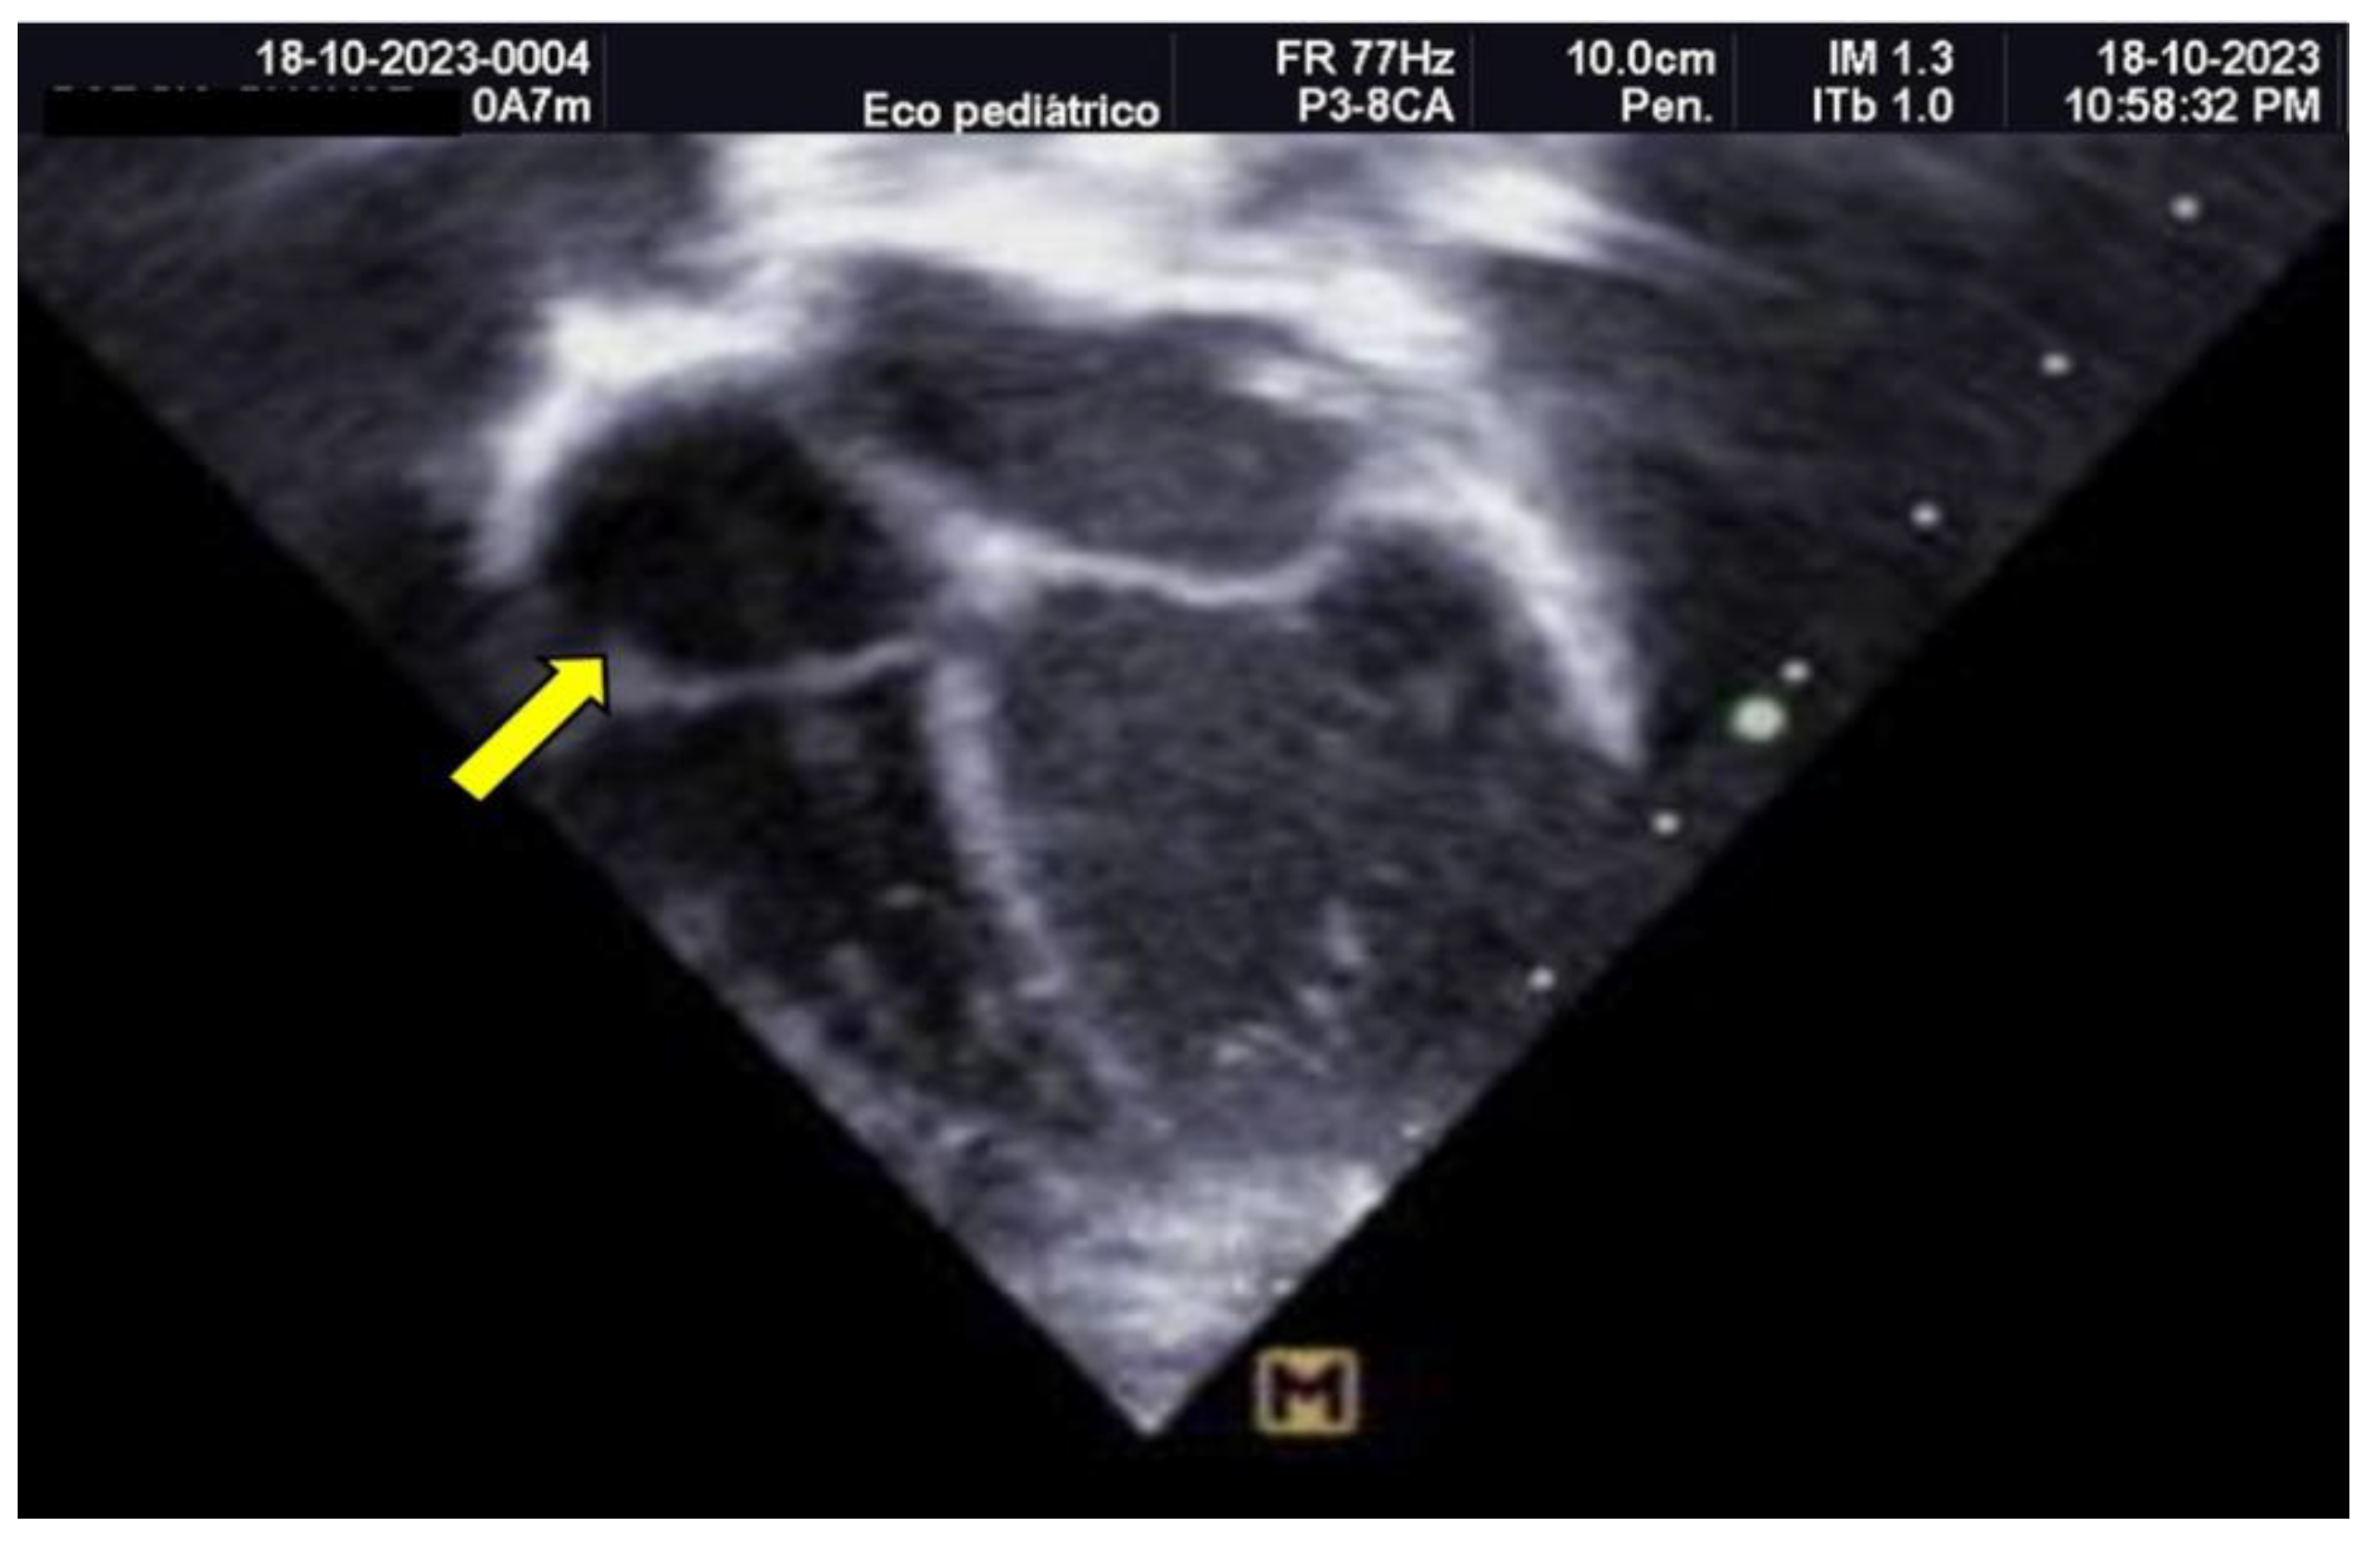

The neonate was referred to Hospital General de Cancún due to tachypnea. Oxygen therapy was initiated using a headbox, and a 5 Fr umbilical catheter was inserted without complications. A pediatric cardiology evaluation, prompted by the maternal history of gestational diabetes, revealed asymmetrical septal hypertrophy and a non-obstructive thrombus (measuring 0.94 × 0.83 cm) in the right atrium (as shown in Figure 1).

Figure 1. Transthoracic Echocardiogram, Apical 4-Chamber View Hyperechoic image corresponding to a thrombus measuring 1.1 x 0.86 cm, attached to the roof of the right atrium.